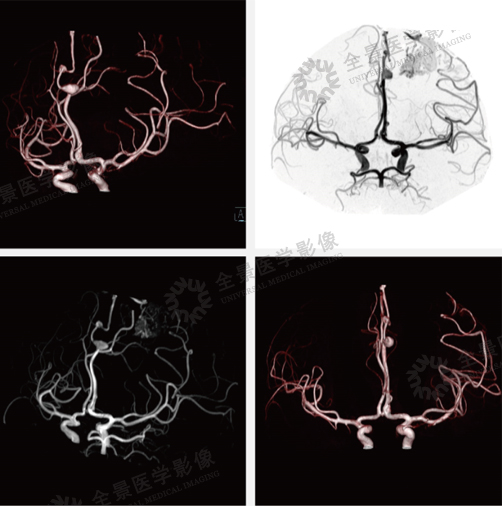

案例:中老年男性,头痛2周,既往有脑出血病史。颅脑MRA示:左侧大脑中动脉及大脑前动脉远段增粗,左侧额叶见畸形的血管团,由左侧大脑中动脉分支参与供血,左侧大脑前动脉分支可疑参与供血。左侧大脑前动脉拼周支分别见梭形扩张及浆果样的动脉瘤,最大直径分别为13mm、5mm,前者呈窄基底与载瘤动脉相连,瘤颈约1mm,后者呈宽基底与载瘤动脉相连。左侧大脑前动脉拼周支两枚动脉瘤。

结论:左侧额叶动静脉畸形(AVM),左侧大脑前动脉动脉瘤。

· 磁共振可以在不打造影剂的情况下,获得三维MRA血管影像,是一种无创伤的血管检查,可以作为DSA的前期筛选和术后的疗效评价。